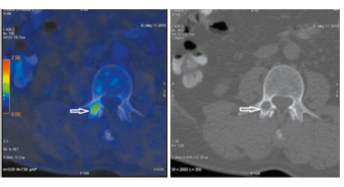

В верхнесуставном отростке третьего поясничного позвонка справа (L3) имеется округлый очаг разрежения костной ткани размером 10×15 мм с разрушением кортикального слоя по внутренней поверхности со стороны

позвоночного канала с повышенной фиксацией радиофармпрепарата с метаболической активностью SUVmax 3.83 (рис. 4).

Рис. 4. Пациент У., 52 года. Аксиальная ПЭТ/КТ- (а) и КТ-проекция (б). В верхнесуставном отростке L3 очаг деструкции размером 10х15 мм (стрелка), SUVmax 3.83.

Fig. 4. A 52-year-old patient U. PET/CT (a) and CT images in axial projection (b). The lytic lesion (10×15 mm) (arrow) in right superior L3 articular process, SUVmax 3.83.